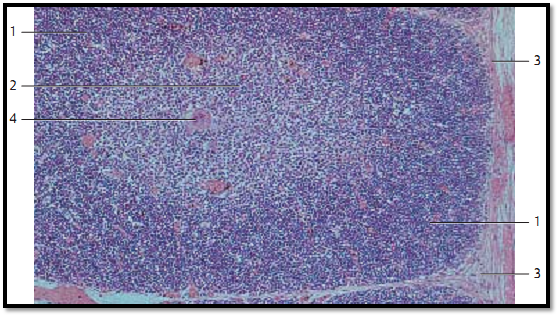

Thymus

The thymus is derived from the pharyngeal pouch. In relationship with other lymphatic organs, it takes a central, superordinate place. In a histological cross-section, the infantile thymus is seemingly built of lobes. Each lobule consists of a corte x 1 (stained blue-violet), which is rich in lymphocytes, and the medulla (stained lighter and reddish) with lower cell density 2 . Vascularized connective tissue 3 , 4 fills the spaces between lobules. It also pushes into the organ, up to the border between cortex and medulla, forming septa (trabeculae). Meshwork s of reticulum cells (epithelial reticulum cells, lymphoepithelial organ ), not fibers, form the supportive structures for cortex and medulla. The reticular cells have arisen from entodermal epithelium. Small lymphocytes (T-lymphocytes) pre dominate underneath the cortex. The medulla contains mostly lymphoblasts, lymphocytes and epithelial reticulum cells. The thymus also contains mast cells, macrophages and interdigitating dendritic cells. The literature of ten describes six different types of epithelial cells. Lymph follicles with germinal centers do not exist in the thymus.

1 Cortex

2 Medulla

3 Blood vessels

4 Connective tissue

Stain: alum hematoxylin-eosin; magnification: × 10